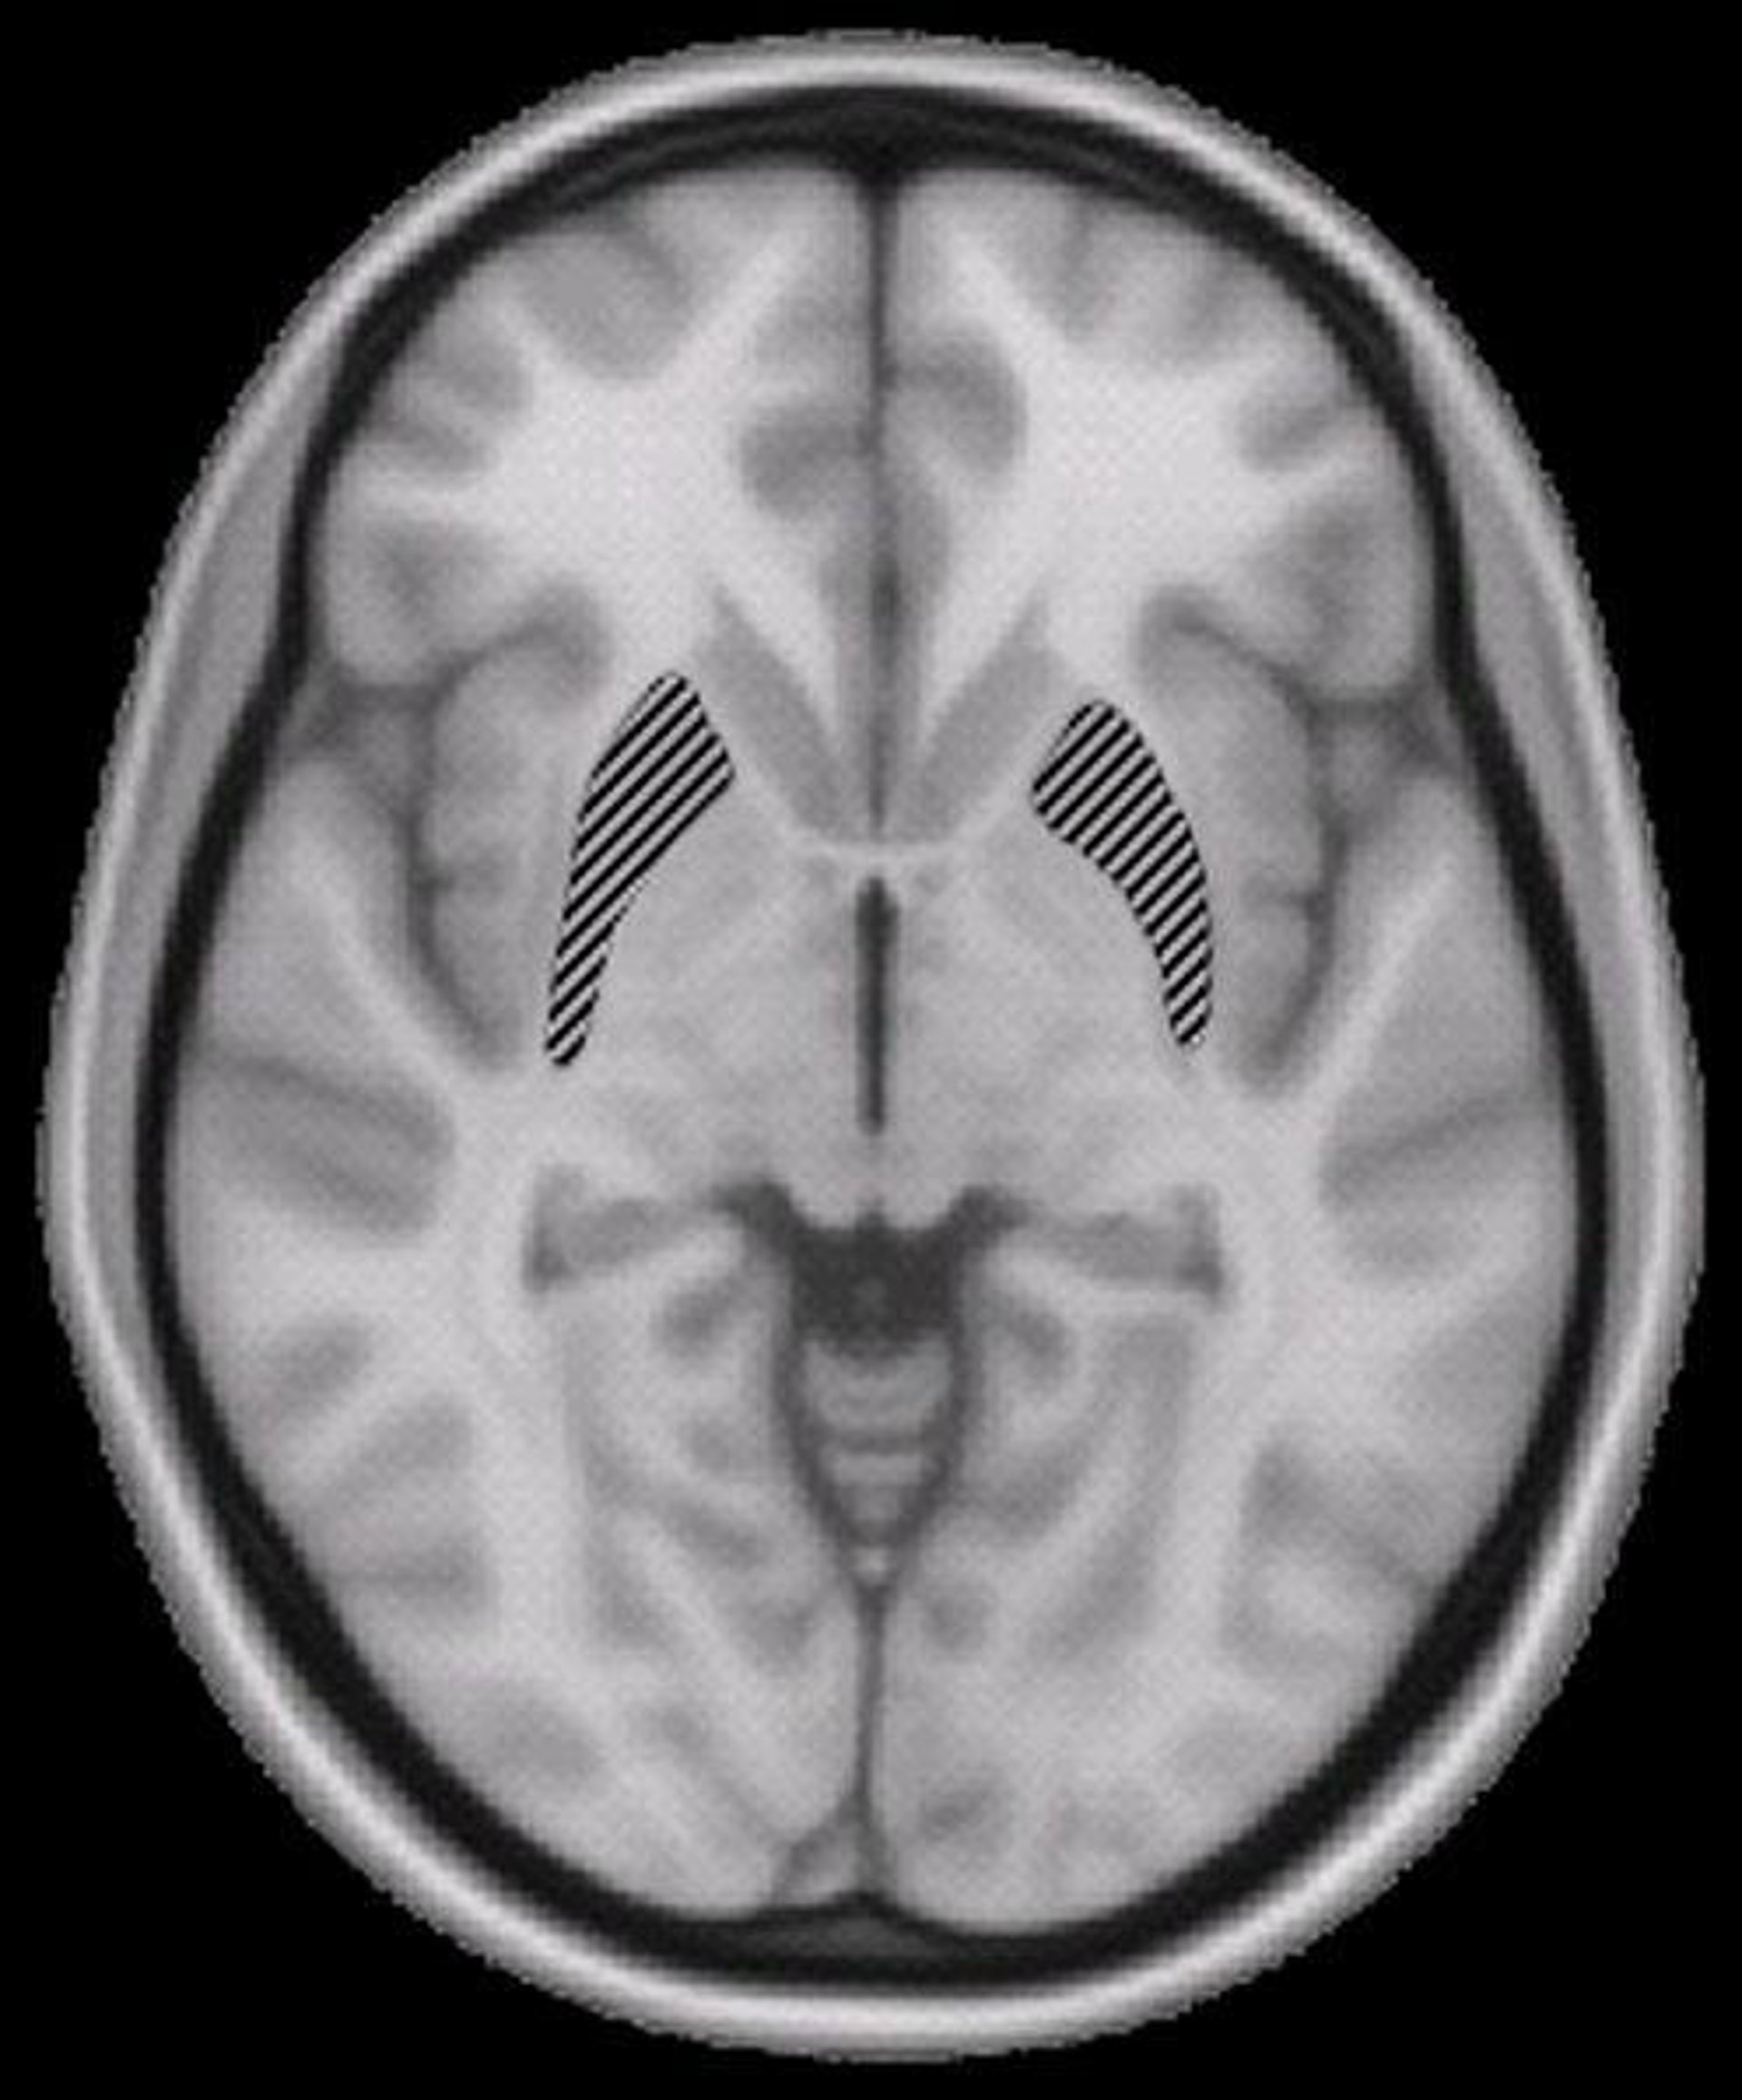

Los investigadores descubrieron que, en vez de residir en una única estructura, la inteligencia general está determinada por una red de regiones en ambos lados del cerebro.

Uno de los principales descubrimientos que impactaron a los científicos fue que existía un sistema distribuido y que varias regiones cerebrales, y las conexiones entre ellas, eran las más importantes para la inteligencia general.

"En realidad, las regiones y conexiones particulares que hallamos están bastante en línea con una teoría existente sobre la inteligencia llamada la 'teoría de integración parieto-frontal", explica el investigador. Esta teoría señala que la inteligencia general depende de la capacidad del cerebro para integrar varias clases diferentes de procesamiento, como la memoria de trabajo.